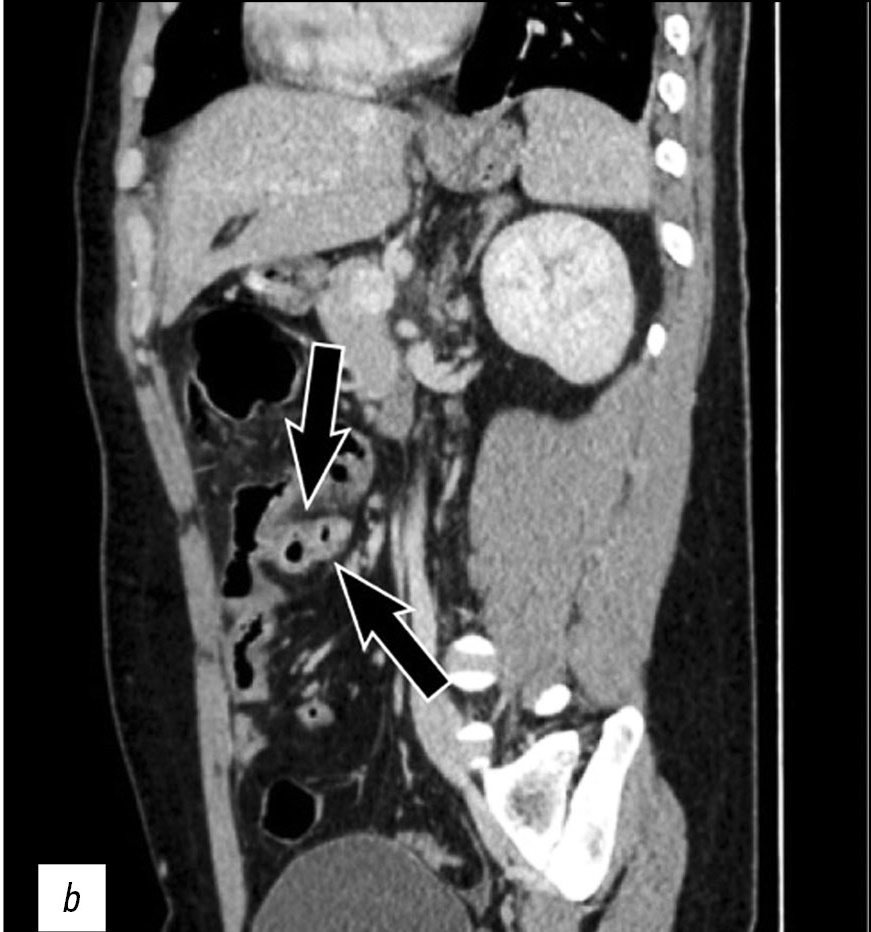

The case of a 26-year-old male patient with perforation of Meckel’s diverticulum, a rare complication of the most common congenital anomaly of the gastrointestinal tract, is reported in this article. This congenital condition can remain asymptomatic for a long time, and it can get complicated with diverticulitis, enteroliths, neoplasms, and rarely perforation, as in this case.

A preoperative radiological assessment is of fundamental importance for proper diagnostic and therapeutic management of the patient. In this article, we present the typical tomographic imaging features of this infrequent complication to assist radiologists in detecting it.